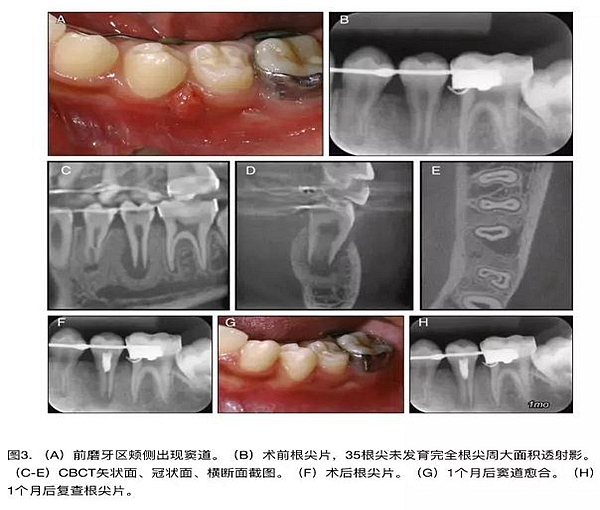

原則上年輕恒牙的牙髓治療應盡可能以保存活髓的方式以便不影響牙根繼續(xù)發(fā)育。本文3個病例均描述了根尖尚未發(fā)育完成的下頜前磨牙被確診為牙髓壞死伴有大面積根尖病損,治療過程中在根管內(nèi)發(fā)現(xiàn)了部分活髓,而采用活髓切斷后都取得了很好的療效。